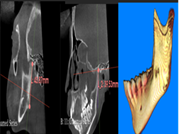

A través de los cortes tomográficos (Figura 3) se pudo observar que la rama mandibular derecha medía 43.85 mm y la izquierda 39.53 mm dando una diferencia de 4.34 mm lo que evidencia que la asimetría que presenta la paciente es a causa de la discrepancia de tamaño de las ramas mandibulares (A).

En el corte a nivel de la articulación temporomandibular izquierda se observó un aplanamiento del cóndilo con áreas de cambios osteoartríticos leves (B); en la articulación temporomandibular derecha el cóndilo se encuentra con una severa osteoartritis que muestra una imagen hipodensa a nivel condilar compatible con un quiste subcondral (C).

Diagnóstico de ATM: La paciente presenta una displasia discal sin reducción bilateral.